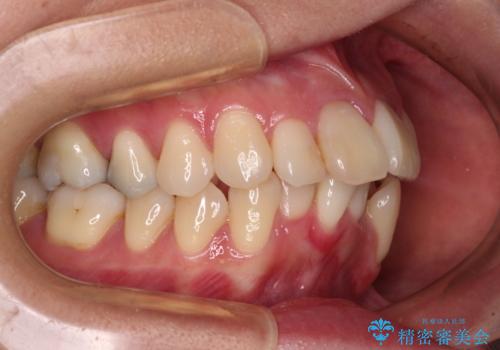

- 八重歯と上の前歯が出っ歯になっていることを気にして来院された患者様です。

横から見た際の口元の飛び出した印象も改善したいとのことで、上下左右の第一小臼歯4本を抜歯し、ワイヤー装置にて抜歯矯正を行うこととしました。

前歯の変色している歯は、神経組織が壊死していたため、矯正治療前に根管治療を実施し、矯正治療後にオールセラミッククラウンにて補綴治療を行うこととしました。